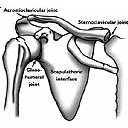

shoulder joint.jpg